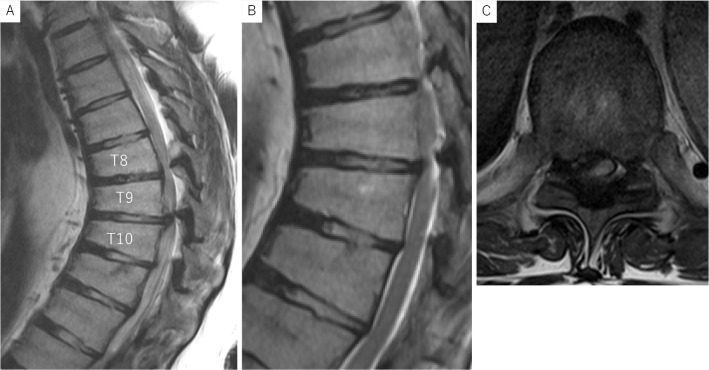

Thoracic Myelopathy with Scheuermann's Disease and Ossification of the Yellow Ligament: A Case Report.